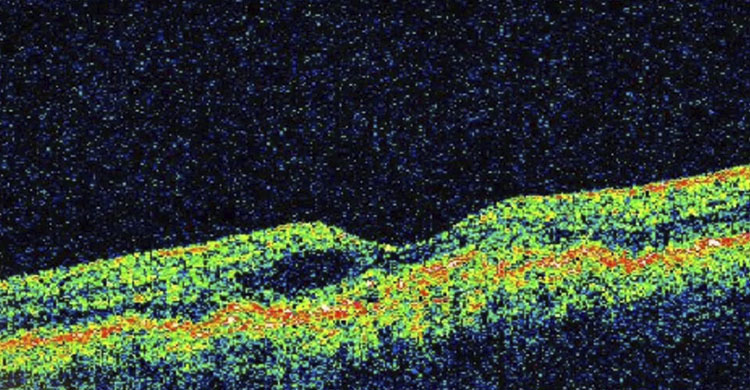

La Academia de Ciencias de la República Dominicana, a través de su Comisión de Ciencias de la Salud, anunció la proyección del video titulado “Enfermedades maculares y su impacto”, una iniciativa orientada a educar y sensibilizar a la población sobre las afecciones que afectan la mácula y su repercusión en la calidad de vida.

La actividad contará con los comentarios especializados de la Dra. Niurka Leonor y el Dr. Juan Ubiera, quienes abordarán los principales aspectos clínicos, preventivos y sociales relacionados con las enfermedades maculares. La moderación estará a cargo del Dr. Herbert Stern, coordinador de la Comisión de Ciencias de la Salud de la institución.

El evento se realizará el martes 24 de febrero de 2026, a las 6:30 de la tarde, en la sede de la Academia de Ciencias, ubicada en la calle Las Damas No. 112, esquina calle El Conde, Zona Colonial, en Santo Domingo.

Con esta iniciativa, la Academia reafirma su compromiso con la promoción del conocimiento científico y la orientación a la ciudadanía en temas de salud pública, especialmente en lo relativo a la prevención y detección temprana de enfermedades que pueden comprometer la visión.